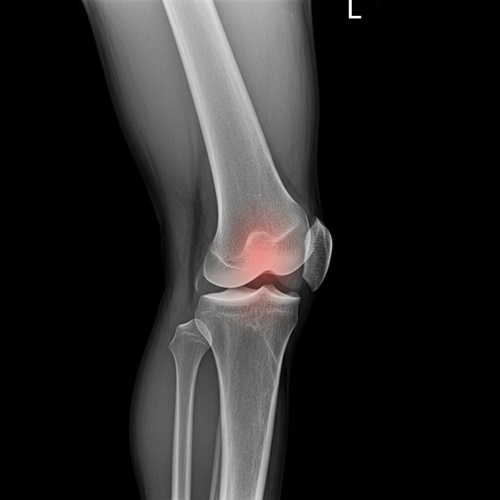

1기는 자각 증상이 거의 없거나 간헐적인 불편함 정도로, 무릎에 약간의 뻣뻣함이 느껴지고 운동 후에만 통증이 있는 경우가 많아요. 이 시기는 엑스레이 검사에서도 큰 이상이 나타나지 않을 수 있어요. 반면, 2기에는 통증이 점점 자주 발생하고, 무릎을 꺾거나 움직일 때 소리가 나거나 저림 증상까지 동반될 수 있어요. 이 단계부터는 엑스레이 상에서 연골의 마모와 관절 간격 감소가 관찰돼요. 무릎 관절염 증상을 이 시점에서 인지하고 적절한 조치를 취하는 것이, 이후 진행을 막는 중요한 전환점이 돼요.

무릎 관절염은 보통 4단계로 구분돼요. 1기는 통증이 거의 없거나 일시적인 수준이고, 2기에는 일상생활 중 통증과 뻣뻣함이 발생해요. 3기부터는 연골 손상이 명확해지고, 4기는 연골이 거의 닳아 관절 간격이 사라지며 극심한 통증과 기능 저하가 나타나요. 무릎 관절염 증상이 반복되고 악화된다면 빠른 진단과 대처가 필요해요.

| 단계 | 주요 증상 및 특징 | X-ray 소견 | 일상생활 영향 |

| 1기 | 거의 통증 없음 또는 가벼운 불편감, 간헐적 뻣뻣함 | 정상 혹은 미세한 연골 마모 | 활동에는 큰 지장 없음 |

| 2기 | 통증 자주 발생, 무릎이 뻣뻣하고 가끔 붓는 느낌 | 관절 간격 약간 좁아짐, 초기 연골 마모 | 계단 오르내릴 때 불편, 오래 걷기 힘듦 |

| 3기 | 지속적인 통증, 무릎을 굽히기 어려움, 마찰음 발생 | 연골 손상 뚜렷, 관절 간격 현저히 좁아짐 | 일상 동작에 제약, 걷기나 일어서기 어려움 |

| 4기 | 극심한 통증, 무릎 변형, 기능 저하 | 관절 간격 거의 소실, 뼈끼리 맞닿음 | 정상적인 보행 어려움, 수술 고려 가능 성 |